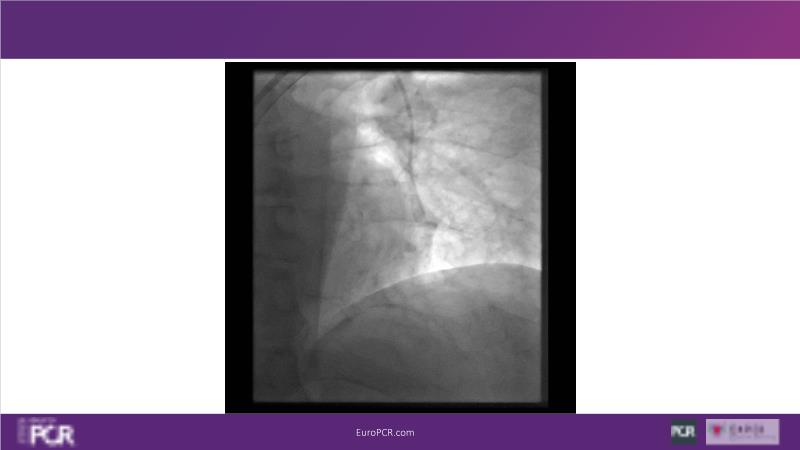

Why mechanical thrombectomy should be considered in the management of acute pulmonary embolism

In this EuroPCR 2024 session, study the case of a patient with high-risk pulmonary embolism and another with intermediate to high-risk pulmonary embolism, delve into discussions on clinical evidence for mechanical thrombectomy in pulmonary embolism, acquire skills to evaluate eligibility for mechanical thrombectomy, and learn how to integrate such technique in local pulmonary embolism patient pathway.